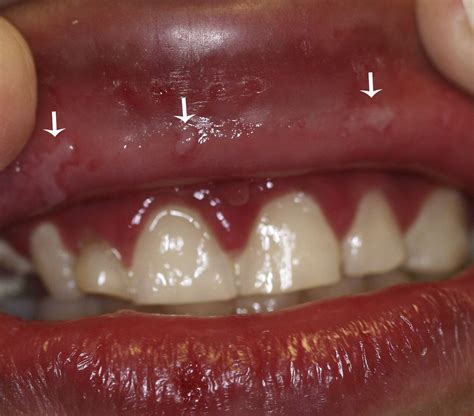

• Sudden gum inflammation: Gums may appear bright red, swollen, and shiny.

• Small, fluid-filled blisters: These can rupture, forming small, painful ulcers on the gingiva.

• Bleeding gums: Even with gentle contact, the inflamed tissue may bleed easily.